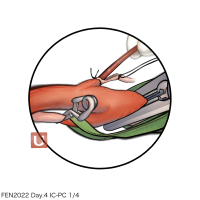

FEN2022シリーズ